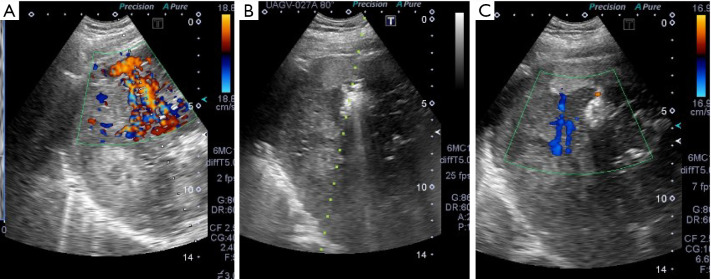

Tract hemostasis using radiofrequency ablation for hepatic arterial bleeding after percutaneous transhepatic portal embolization.